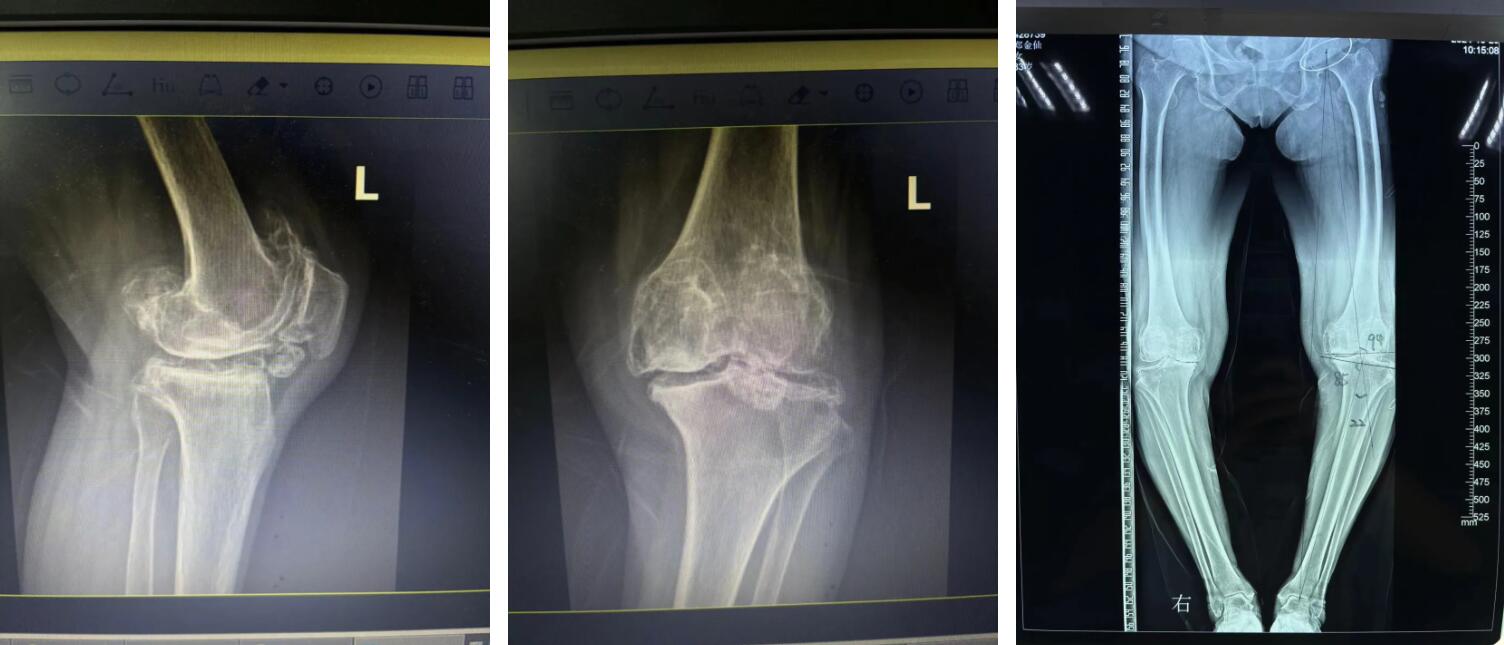

可是現(xiàn)如今阿婆雙膝部的疼痛逐漸加重,膝蓋也嚴(yán)重變形,終日苦不堪言,家里兒女看到后甚是心疼,最終經(jīng)過多方打聽后,鄭阿婆在家人的陪同下來到廣安醫(yī)院找到了關(guān)節(jié)科羅軍副院長(zhǎng)。

羅院長(zhǎng)仔細(xì)了解鄭阿婆的病情后,第一時(shí)間為阿婆確定了左側(cè)人工全膝關(guān)節(jié)置換手術(shù)的治療方向,并制定了詳細(xì)的治療方案,最終得到了阿婆和家屬的一致認(rèn)同。

住院后,羅院長(zhǎng)立即給阿婆安排一對(duì)一術(shù)前規(guī)劃、術(shù)前3D打印,做到了關(guān)節(jié)置換的“量身定制”,最終在羅軍手術(shù)團(tuán)隊(duì)的努力下阿婆順利完成了機(jī)器人輔助下左側(cè)人工全膝關(guān)節(jié)置換手術(shù)治療。